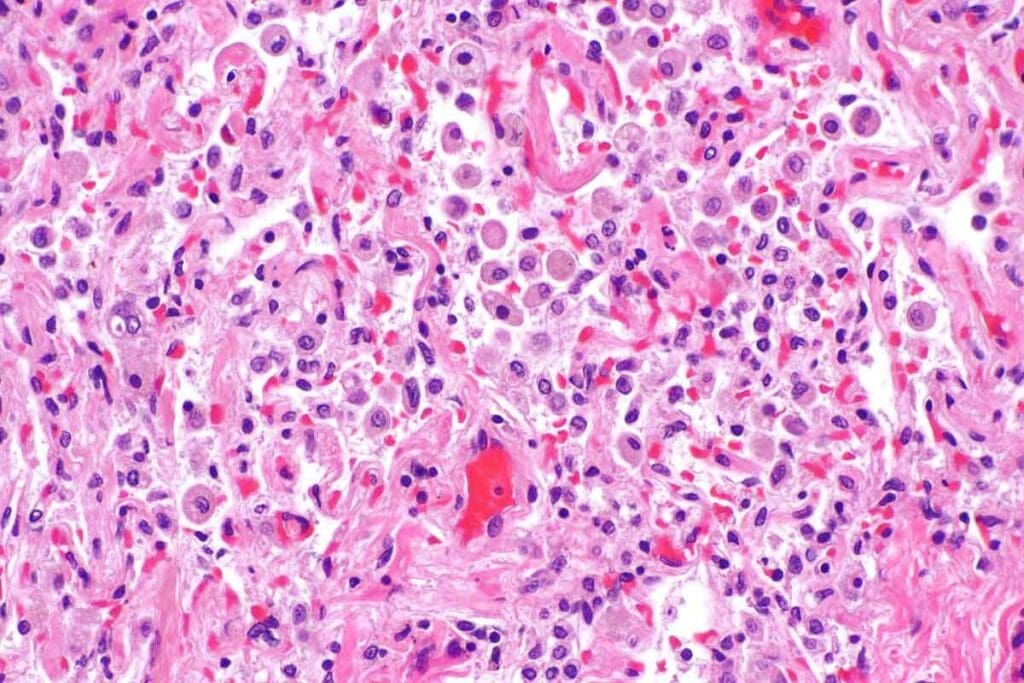

A bone marrow biopsy is a key test. It takes a bone marrow sample for a closer look. This confirms if cancer cells are in the marrow.